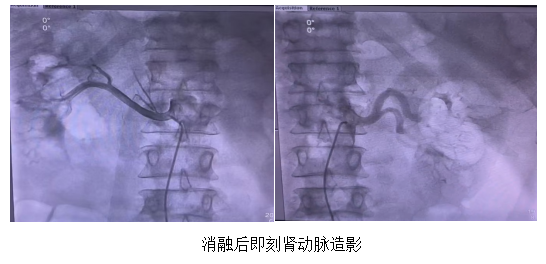

手术中于双侧肾动脉共标测 23 个位点,消融 17 个位点。术前诊室血压 154/88 mmHg,术后即刻血压 133/79 mmHg。手术共花费 1 小时 10 分钟,消融后肾动脉无狭窄、无夹层等并发症,术后第二天监测血压稳定于 120/70 mmHg。手术获得圆满成功。